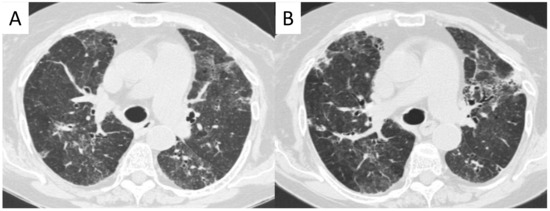

2.10.2. Morphological Patterns and Imaging

2.5. Eosinophilic Granulomatosis with Polyangiitis (EGPA-Churg-Strauss)

| EGPA | Migrant GGOs, transient consolidation, irregular bronchial wall thickening, small nodules with peribronchial and centrilobular distribution, pleural effusion. |